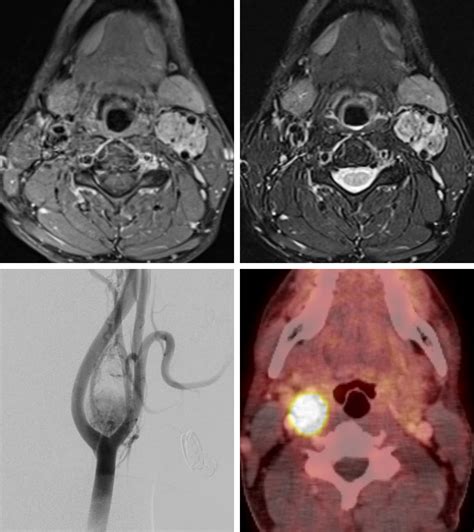

Diagnosing a Carotid Body Tumor requires a combination of physical examination and advanced imaging studies. When a physician suspects such a growth, they typically use specific diagnostic tools to differentiate it from enlarged lymph nodes or other neck masses. The “Lyre sign,” seen on imaging, is a classic finding where the internal and external carotid arteries are splayed apart by the tumor mass.

Magnetic Resonance Imaging (MRI) Offers excellent soft-tissue contrast to identify involvement of nerves.

Catheter Angiography The "gold standard" for identifying the blood supply and planning potential embolization.

The primary treatment for a Carotid Body Tumor is surgical resection. Due to the high vascularity of the tumor, surgeons often perform preoperative embolization, which involves injecting a substance into the tumor’s blood vessels to block the supply. This step significantly reduces the risk of excessive bleeding during the main operation.